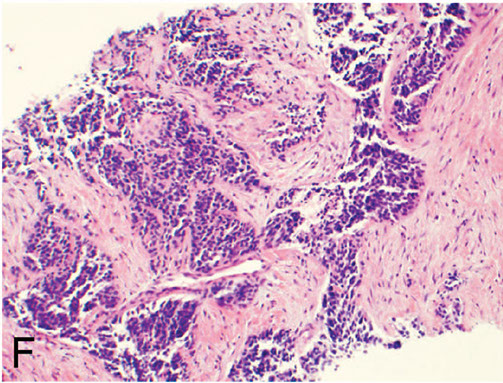

Micro: malignant bone stroma with lacy-patterned matrix that at least focally produces osteoid surrounding neoplastic mesenchymal cells and is infiltrating the marrow spaces bwt mature trabeculae

- can see atypical mits (atypical mits NEVER in b9 conditions [?])

- normalization: atpia is less in oseoid islands than in surrounding malignant stroma

Any amount of neoplastic matrix automatically upgrades a lesion to osteosarcoma

MC subtype is conventional high-grade type (made mostly of osteoblastoma; 75-85%); then high-grade secondary osteosarcoma (10%) and surface osteosarcoma (5-10%) - [chondroblastic {makes cartilage}, fibroblastic {no matrix production}, small-call or giant-cell rich]

Osteosarcoma